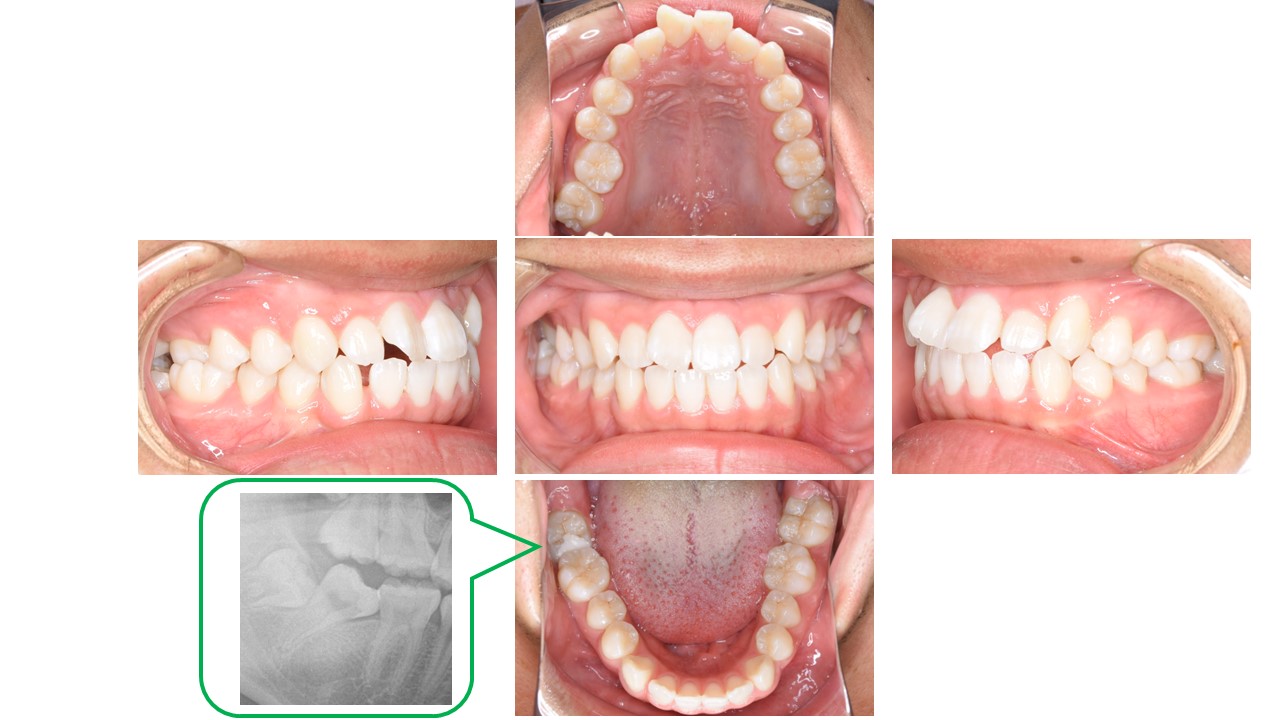

ガタガタ、奥歯のかみ合わせを治したい(16歳男性 治療期間:1年11か月)

症状 上顎前歯翼状捻転・右側6鋏状咬合・下顎右側7近心傾斜により萌出困難 年齢・性別 初診時年齢 16歳2か月 男性 治療期間 1年11か月・通院回数計24回 治療方法 抜歯部位なし・マルチブラケット装置 費用 88万円(検査・診断・通院費込み)矯正歯科治療は公的健康保険の対象外の自費診療となります。 デメリット・注意点 歯の移動に伴う歯肉退縮や歯根吸収(この患者様では認められず)、清掃不良により一時的な歯肉腫脹 備考 診断名:下顎の左方偏位を伴う叢生 -

かかりつけ医でガタガタと右下の奥歯の傾斜を指摘され、当院に来院されました。

幼少期に受け口の治療と、舌小帯切除の既往があります。

初診時は叢生に加え、前歯部のかみ合わせも浅く、下顎骨の左方偏位が認められました。

叢生量が多くないため、非抜歯で治療を行いました。

下顎骨の左方偏位があるため、上下の歯列正中は一致しきれていませんが、良好な咬合関係となりました。

現在プレートタイプのリテーナーで保定を行い、保定中に親知らずを抜去予定です。